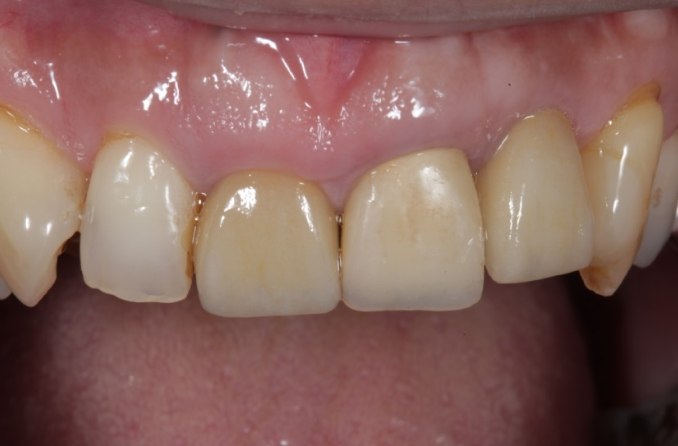

症例3

| 項目 | 詳細 |

|---|---|

| 患者様データ | 40代 男性 |

| 来院時の主訴 | 「前歯を歯磨きすると痛いし、出血する。」 |

| 医院の診断 | 右上中切歯根尖性歯周炎、歯周病 |

| 通院期間 |

6か月 |

| 来院回数 | 10回 |

| 治療費 | 総額:歯周病治療に関しては保険適用診療。その他:370,000円(税抜) 【内訳】 歯周病治療(歯周病検査・歯磨きや生活習慣指導・歯石取りクリーニング) その他、精密根管治療 70,000円、ファイバーポストコア 20,000円、セラミック治療 140,000円×2 |

| リスクと副作用 | メインテナンスが必要、正しい歯磨き習慣が必要不可欠 |

| ここがこだわりのポイント!☝ | こちらは中等度の歯周病と虫歯を併発されていた患者様です。日々の歯磨き習慣を見直していただき、正しいブラッシング法を身につけたことで健康な歯肉を取り戻しました!短期間での治療を希望されていたので審美的な歯肉ラインの獲得はできませんでしたが、健康的な歯肉を獲得できました。 |